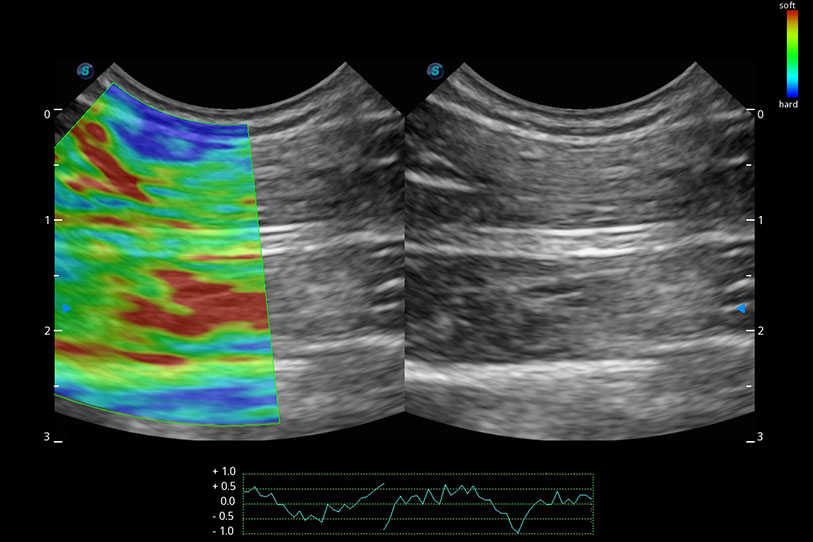

操作簡便,無需高頻度外力作用即可真實反映組織的形變,快速評估腫瘤良惡性。